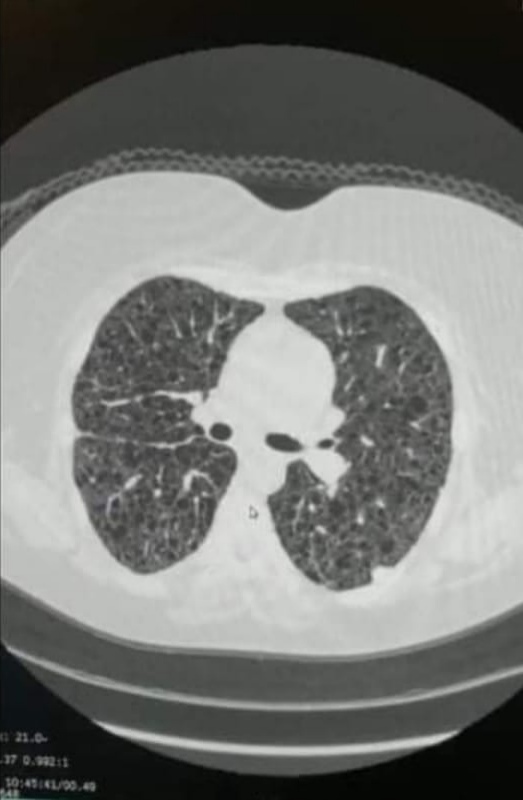

وقالت نجوى عبد اللطيف والدة المريضة في تصريحات خاصة لـ القاهرة 24: اكتشفنا المرض منذ 9 سنوات عندما بدأت حالة ابنتي تتدهور تدريجيا وإحساس كالسكاكين بالصدر، والذي كان نتيجة انفجار تكيسات الرئة ولم نكن نعلم، فلم يتم التشخيص إلا بعد انثقاب الرئتين، ومع الفحص تبين أنها مصابة باسترواح بالصدر الأيسر مع انصباب بلوري لمفاوي متكرر.

وتابعت: هذا المرض – الورم العضلي اللمفي - نادر جدا ينتج عن حدوث طفرة في جينات TSC1 أوTSC2 مما يسبب تورما عضليا أملس في الرئتين مع فشل مزمن بالجهاز التنفسي، نسبة انتشار المرض ضئيلة جدا تقريبا 4:3 حالات لكل مليون أنثى.

وأوضحت عبداللطيف: بنتي في المرحلة الأخيرة من المرض. حيث يبلغ متوسط العمر المتوقع بعد تشخيصها من 8-10 سنوات ولكن توضح تقارير أخرى امتداد فترة البقاء على قيد الحياة لـ20 عاما، وهي الآن أسيرة سرير بالمستشفى منذ 3 سنوات، فقد ظلت حالتها تتدهور حتى أصيبت بفشل رئوي، فالرئة تعمل حاليا بنسبة 10% فقط.